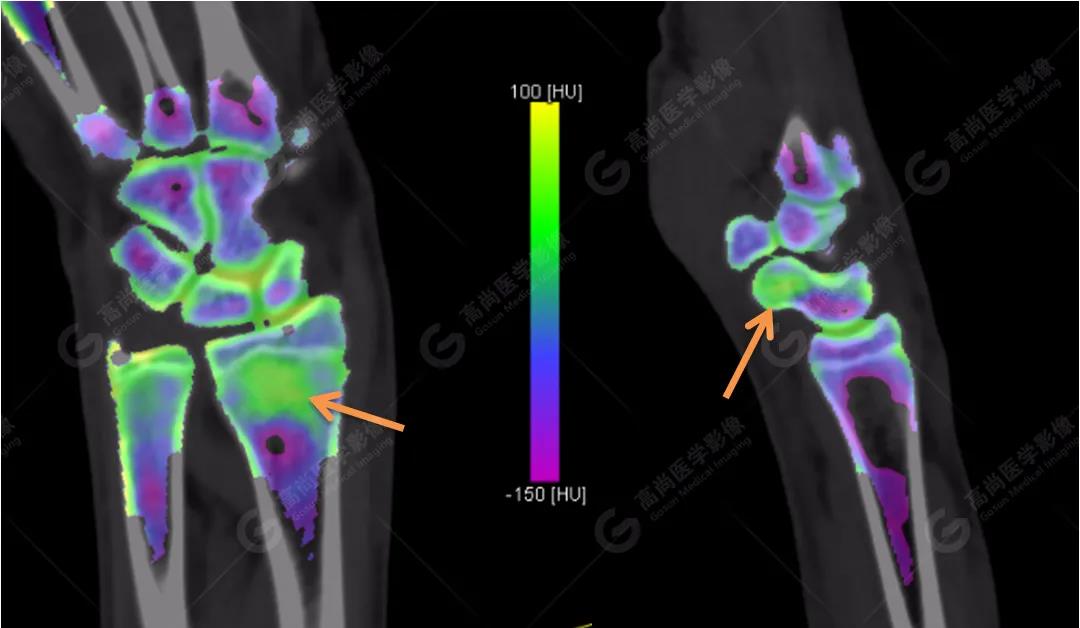

3、雙能CT骨髓成像(雙能虛擬去鈣圖像)

高尚醫(yī)學影像診斷中心的Flash雙源CT可以利用雙能量骨髓成像來顯示骨骼內(nèi)的骨髓水腫,而外傷性的骨髓水腫往往提示骨挫傷或小梁微骨折。重建一下雙能虛擬去鈣骨髓圖像,進一步排除骨挫傷、微骨折。

雙能CT骨髓成像圖上發(fā)現(xiàn)了左側(cè)橈骨遠端和右側(cè)舟狀骨骨髓水腫(箭頭所示),進一步查體這兩處骨髓水腫剛好與患者的局部壓痛點相一致。